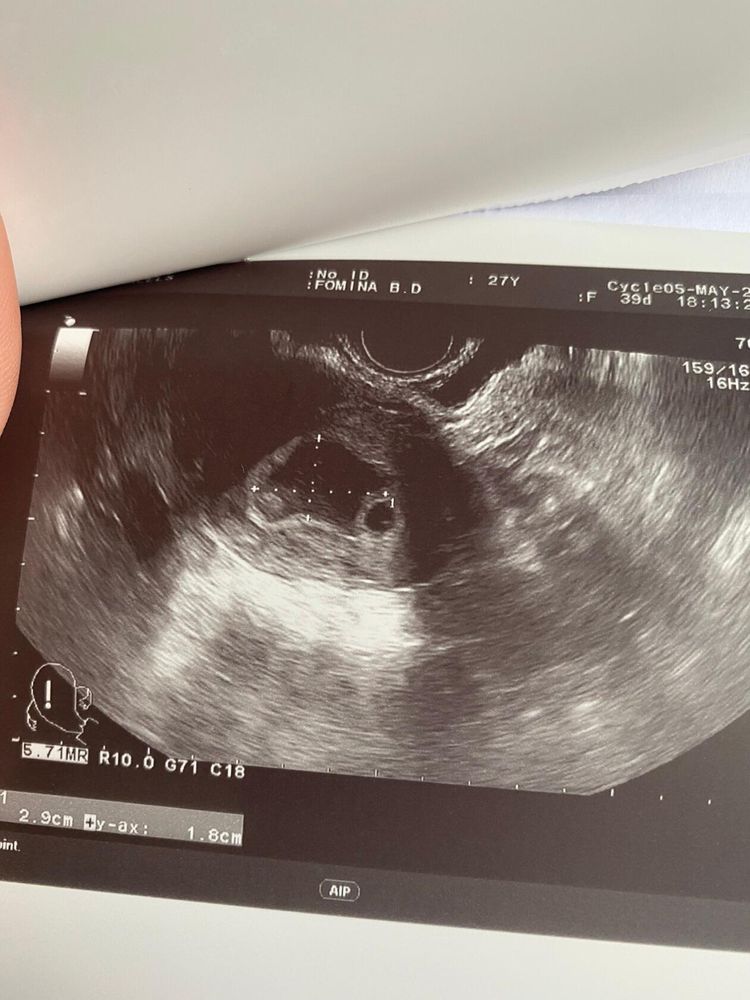

25 дпо узи

Сходила сегодня на узи, завтра ложусь в больницу((( Огромная гематома . Моя гинеколог говорит, что такое чувство что хотели начаться месячные , началась отслойка ( когда кровило на 12 и 13 дпо) , но мы их остановили . Так что я всегда за то, чтобы все-таки делать тесты до задержки , вот если бы я не узнала, что беременность есть, то просто бы подумала,что начались месячные . Без дюфа говорит мне тоже никак.

вот сдесь на фото сверху видно мою огромню гематому и справа снизу плодное яйцо